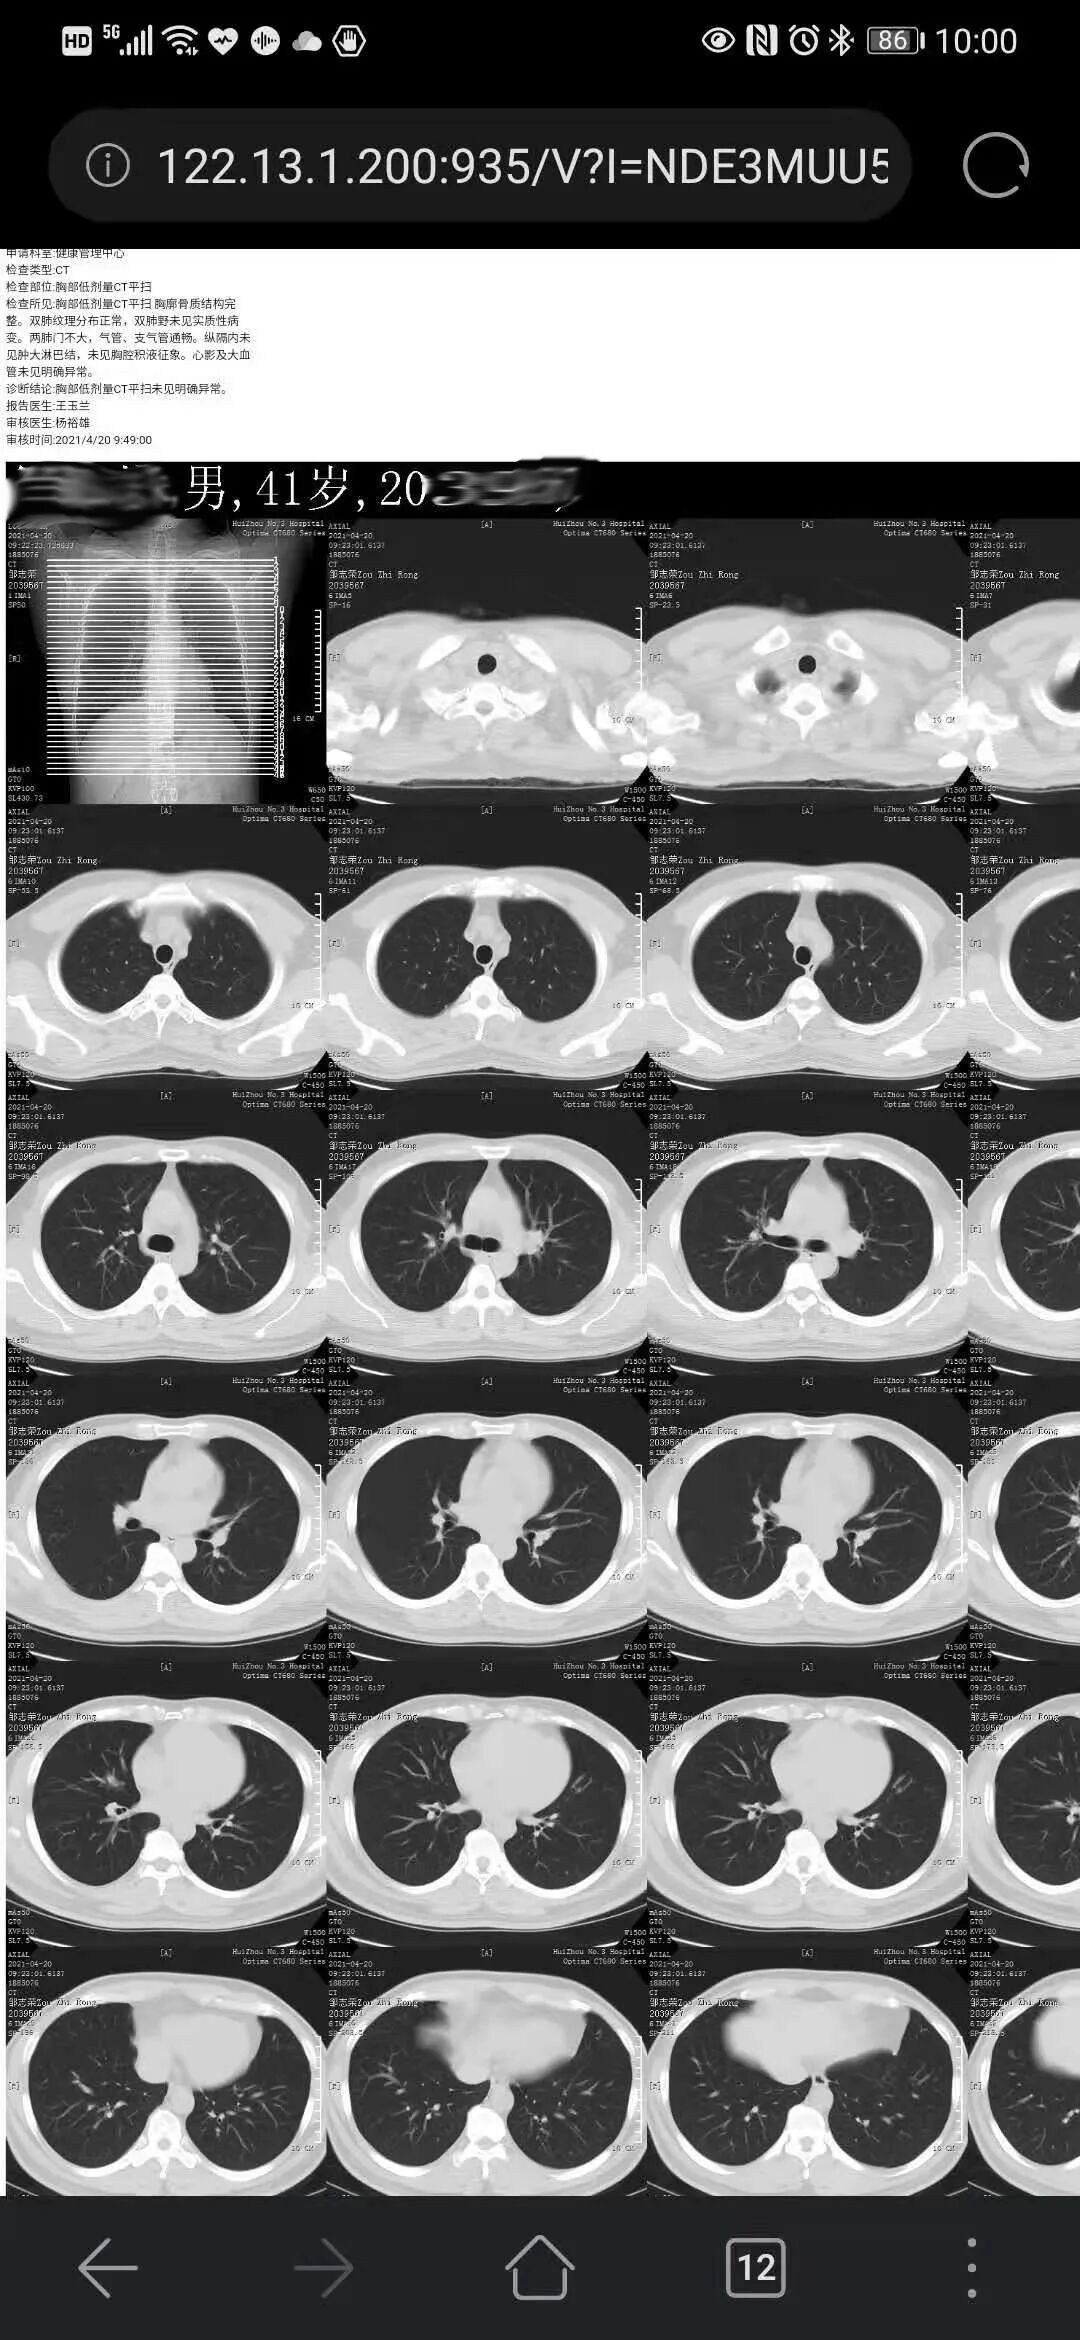

@惠州市民 手機(jī)上也能查閱膠片啦!惠州三院便民惠民新舉措,“云膠片”6月起上線!